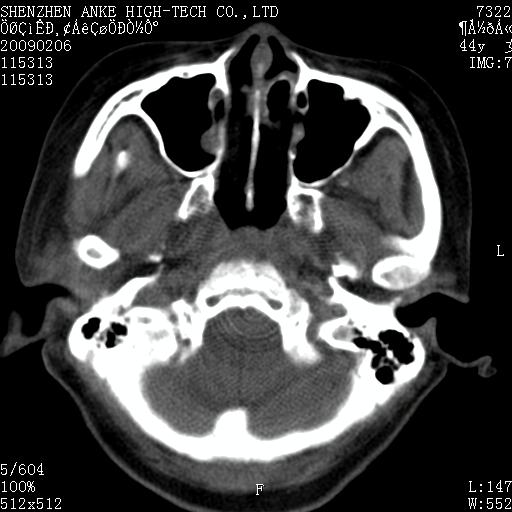

标题: CT17977:女,44岁,右侧颌部包块1年,右侧面瘫2月。 [打印本页]

患者:女,44岁,右侧颌部包块1年,右侧面瘫2月。

考虑右侧腮腺混合瘤可能性大

考虑右侧腮腺混合瘤;不排除腮腺癌。

右侧腮腺肿瘤,良恶性难定。